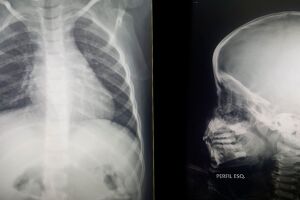

O bebê nasceu e chegou a ficar 18 dias internado por conta de plaquetas baixas. Desde a alta, precisa de acompanhamento e exames que, segundo a mãe, não foram solicitados por falta de pediatra na unidade.